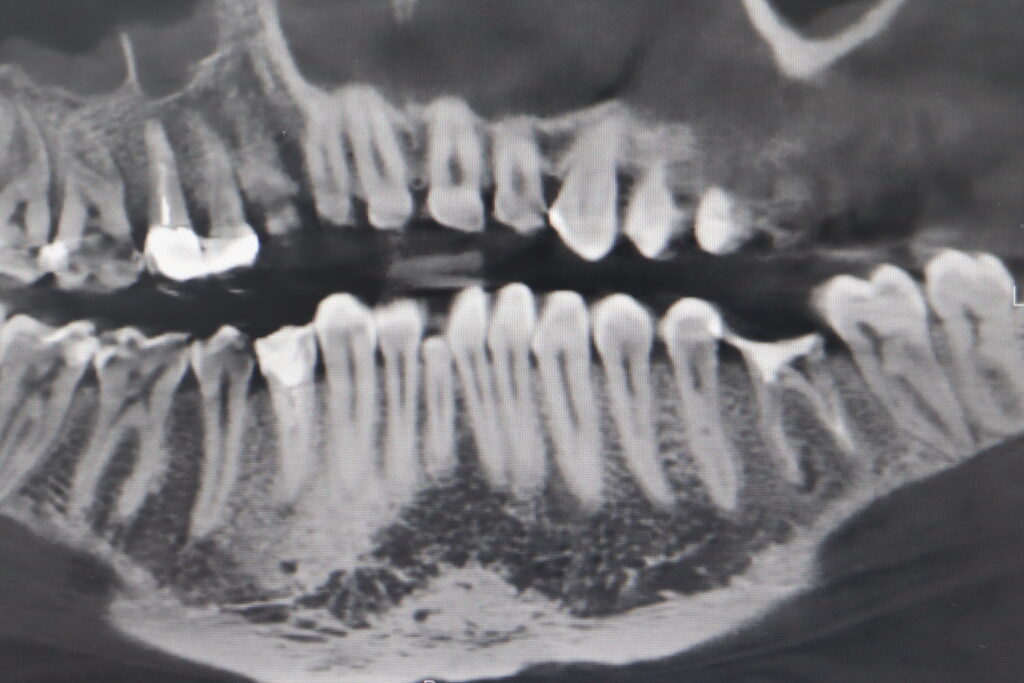

пациент до имплантации